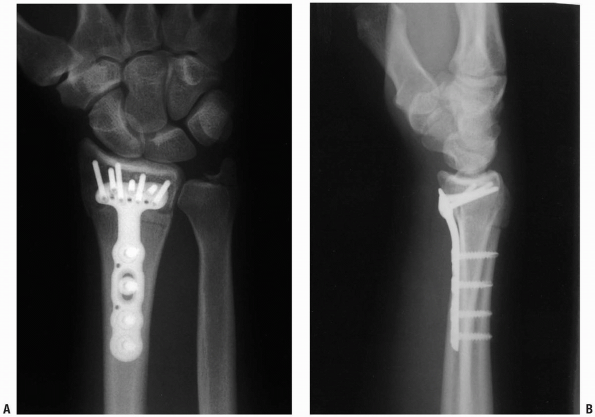

The pronator quadratus is released (Fig. 1-39) and reflected from the distal radius from a radial to ulnar direction with attached periosteum (Fig. 1-40).

-

With different forms of distraction

(finger traps or an occasional external fixator), alignment of the

distal radius fracture is obtained and the plate is applied (Fig. 1-41). Percutaneous pins are inserted to hold the fracture in alignment. -

Appropriate x-rays are taken to ensure

that the fracture is adequately reduced and then one of a variety of

volar fixation plates is applied (Fig. 1-42).

![]() |

|

FIGURE 1-42 Posteroanterior (A) and lateral (B)

x-rays of the distal radius after plate fixation. Note lateral view position of screws proximal to the radiocarpal joint articular surface. |